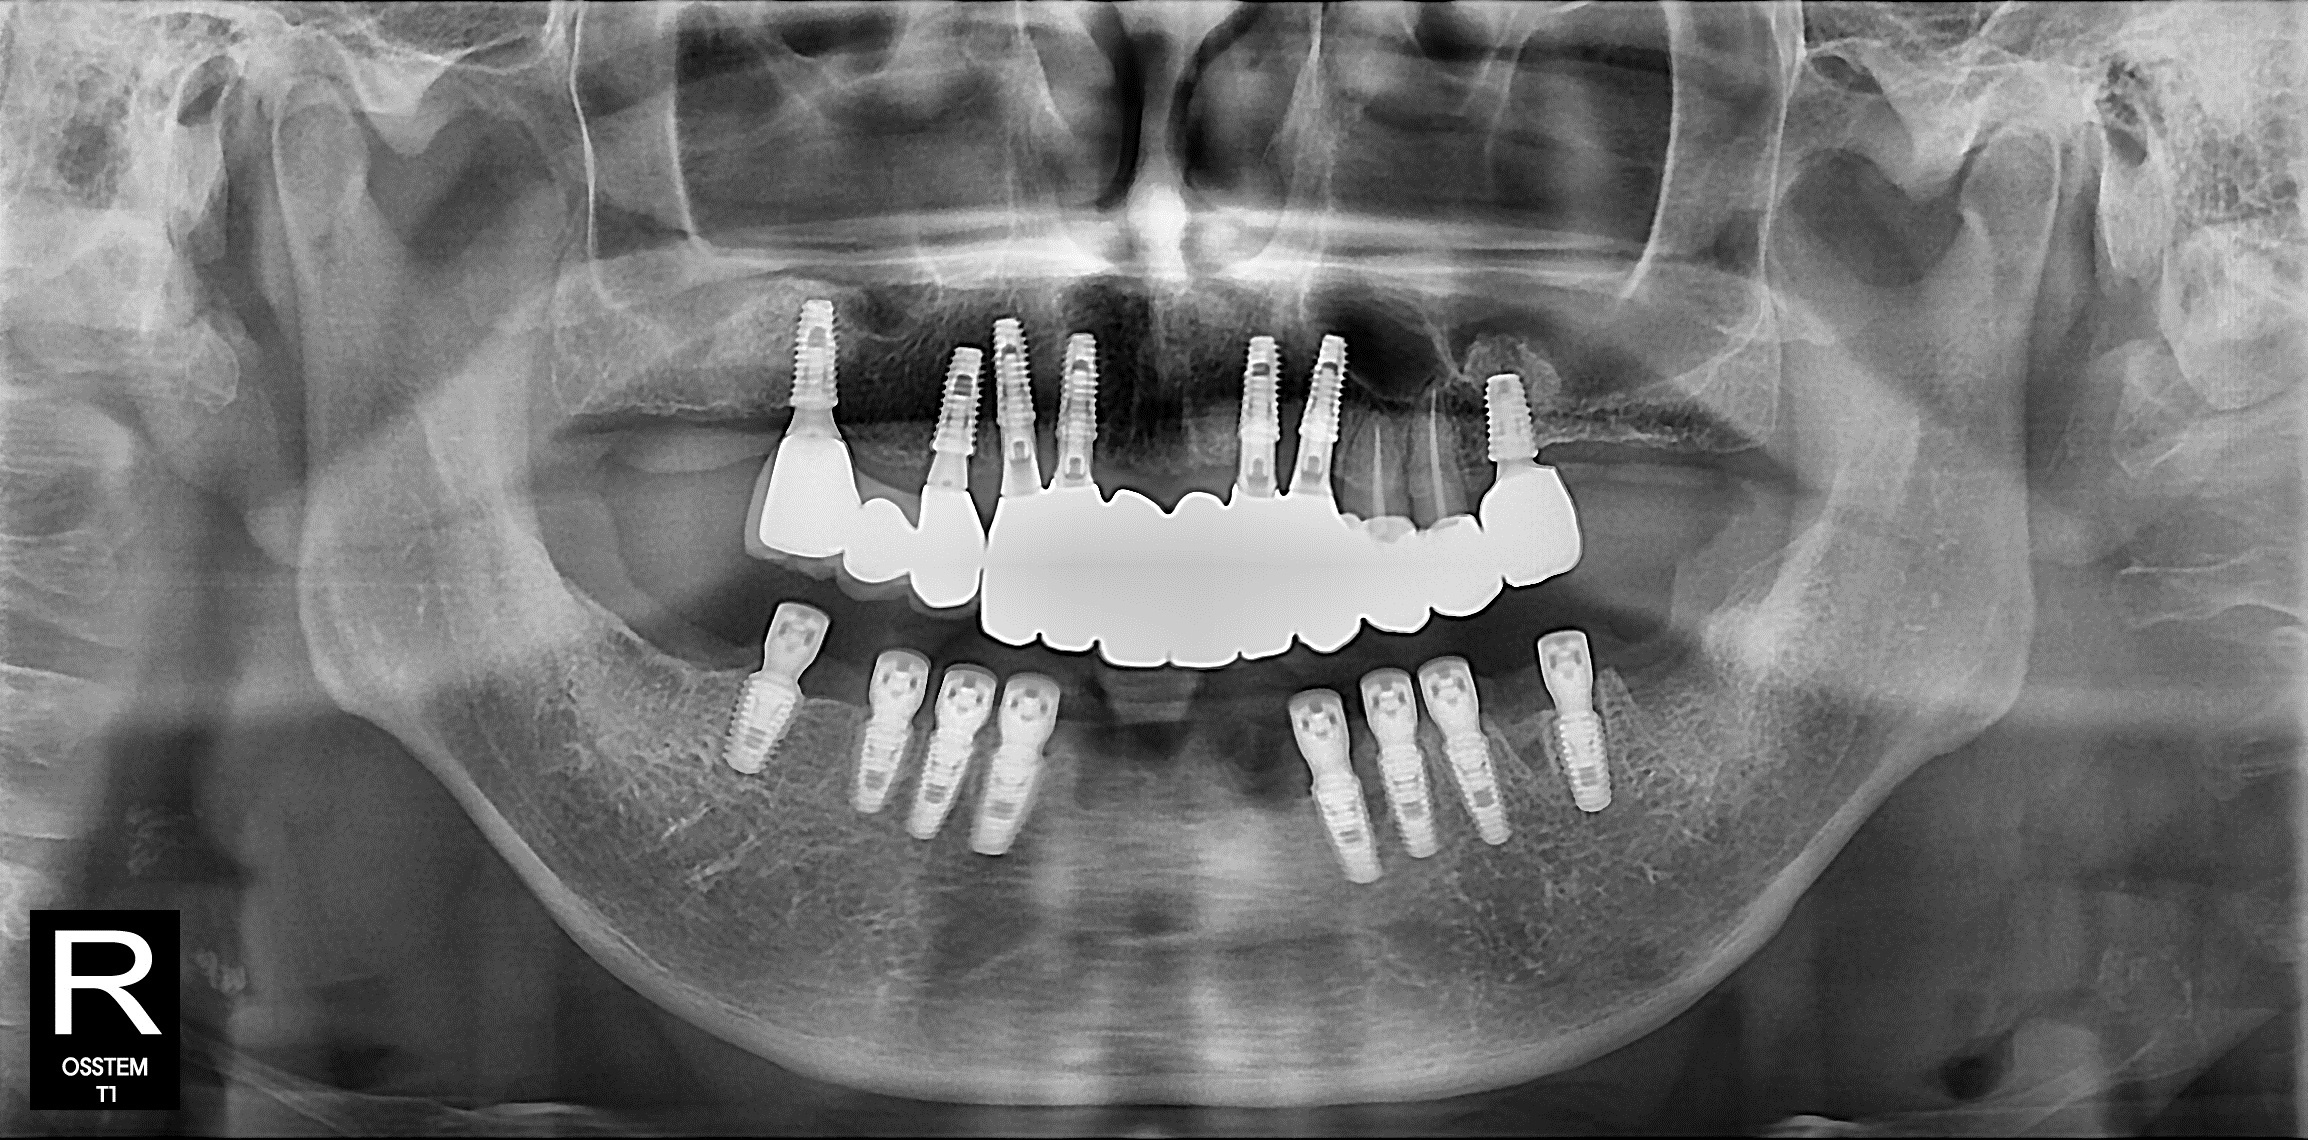

엑스레이를 찍어보니,

아래 앞니는 풍치로 인해

잇몸뼈가 많이 녹아 있었고

아래 어금니 쪽도

이미 뼈 흡수가 진행된 상태였습니다.

전체적으로 치아가 이제는

버티기 어려운 단계라고 할 수 있죠..

발치 12개임플란트 8개 식립

한 번에 진행했습니다.

이 과정은 속도싸움이 아니라

각도·깊이·초기 고정력

모두 고려해야 하는

고난도 수술이였습니다.